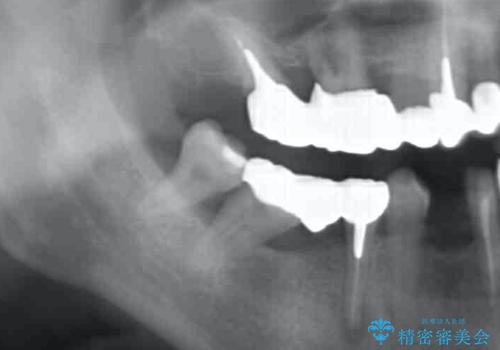

- これまで悪くなっては歯医者に通い、その都度治療を受けてきたがどんどん悪くなる痛くてしっかりと噛めない、これを機にしっかりと噛めるような治療を受けたいと希望され来院されました。

保存不可能な歯の抜歯→インプラント治療、根管治療、精密なセラミッククラウンの製作を行い長期的に安定し、審美的で機能的な治療を計画します。

歯が悪くなるたびにその都度治療を行うと、付け焼き刃の治療となりやすくまた横の歯が悪くなってしまった場合に再治療が必要となったり延々と治療が続くことがしばしばです。

隣接する歯や、残すことのできない歯をインプラントにしっかりと置き替えていくことで安心して長期にしっかりと噛める口腔内環境を達成することができます。